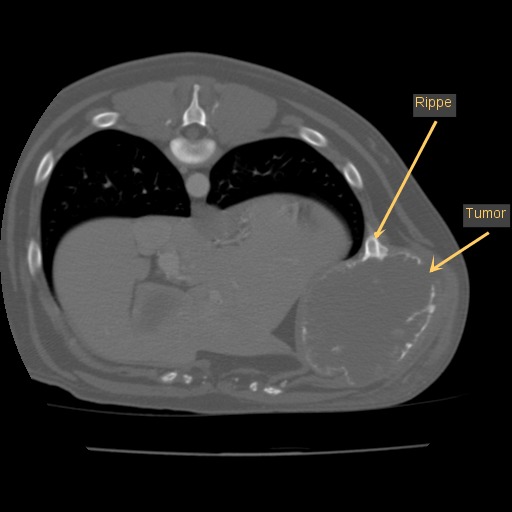

Da die Umfangsvermehrung jedoch weiter wuchs, wurde eine Gewebeprobe mit einer dickeren Stanznadel entnommen. Dies ergab schließlich die endgültige Diagnose „Chondrosarkom“, ein bösartiger Tumor, der vom Knorpelgewebe ausgeht. An dieser Stelle des Körpers entstehen diese Tumoren aus dem bauchseitigen knorpeligen Ende der Rippen.

Bei Vorstellung in der Tierklinik Oberhaching war die Umfangsvermehrung schließlich schon tennisballgroß und sehr derb. Ein vom Haustierarzt angefertigtes Röntgenbild wies bereits auf eine teilweise Auflösung des knöchernen Anteils der elften Rippe hin. Das Allgemeinbefinden des Hundes war ungestört, er war bei gutem Appetit, die Umfangsvermehrung hat ihn nicht weiter gestört.

Leo wurde nun nach einer gründlichen allgemeinmedizinischen sowie labortechnischen Untersuchung zur Computertomographie (CT) angemeldet, die in Vollnarkose stattfinden muss. Mit dieser Technik werden mit Hilfe von Röntgenstrahlen ein Millimeter dünne Schichtaufnahmen angefertigt und damit das genaue Ausmaß des Tumors dargestellt. Zum anderen kann im Vergleich zu einem konventionellen Röntgenbild eine überlagerungsfreie Aussage über den Zustand des benachbarten Weichteilgewebes getroffen werden. Diese Informationen sind für den Chirurgen unumgänglich, damit er die Operation planen kann.

In diesem Fall wurde durch die CT das enorme Ausmaß der Umfangsvermehrung deutlich, sodass insgesamt drei Rippen inklusive der dazwischenliegenden Muskeln in Mitleidenschaft gezogen wurden. Die gute Nachricht war, dass der innerhalb der Bauchhöhle unmittelbar anliegende linke Leberlappen, Magen und Milz sowie der hintere Anteil des linken Lungenflügels im Brustkorb noch nicht vom Tumorwachstum erfasst waren.